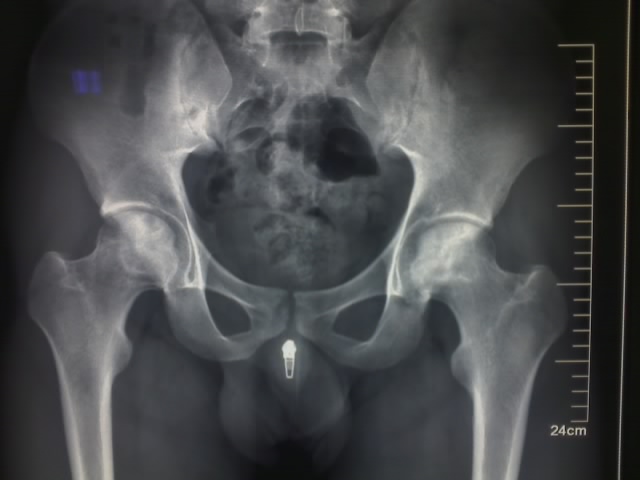

双股骨头无菌坏死明确,双侧骶髂关节改变,青年男性可考虑as及其他血清阴性关节炎,加拍脊柱等其他部位,结合实验室检查。

as可造成关节面软骨及软骨下骨的侵蚀破坏,尤其双侧髋关节,但渗出变化轻而增值性变化重,明显纤维增值后,可出现关节内骨性强直及关节囊钙化骨化。本例股骨头改变还是考虑无菌性坏死。

双股骨头密度增高,其中多发低密度影,双骶髂骨节面模糊,密度增高。支持股骨头无菌性坏死,诊断血清阴性骨关节病较合适。病史?症状体征?楼主舒服大家就辛苦了

强直性脊柱炎骶髂关节、髋关节改变可能大 。